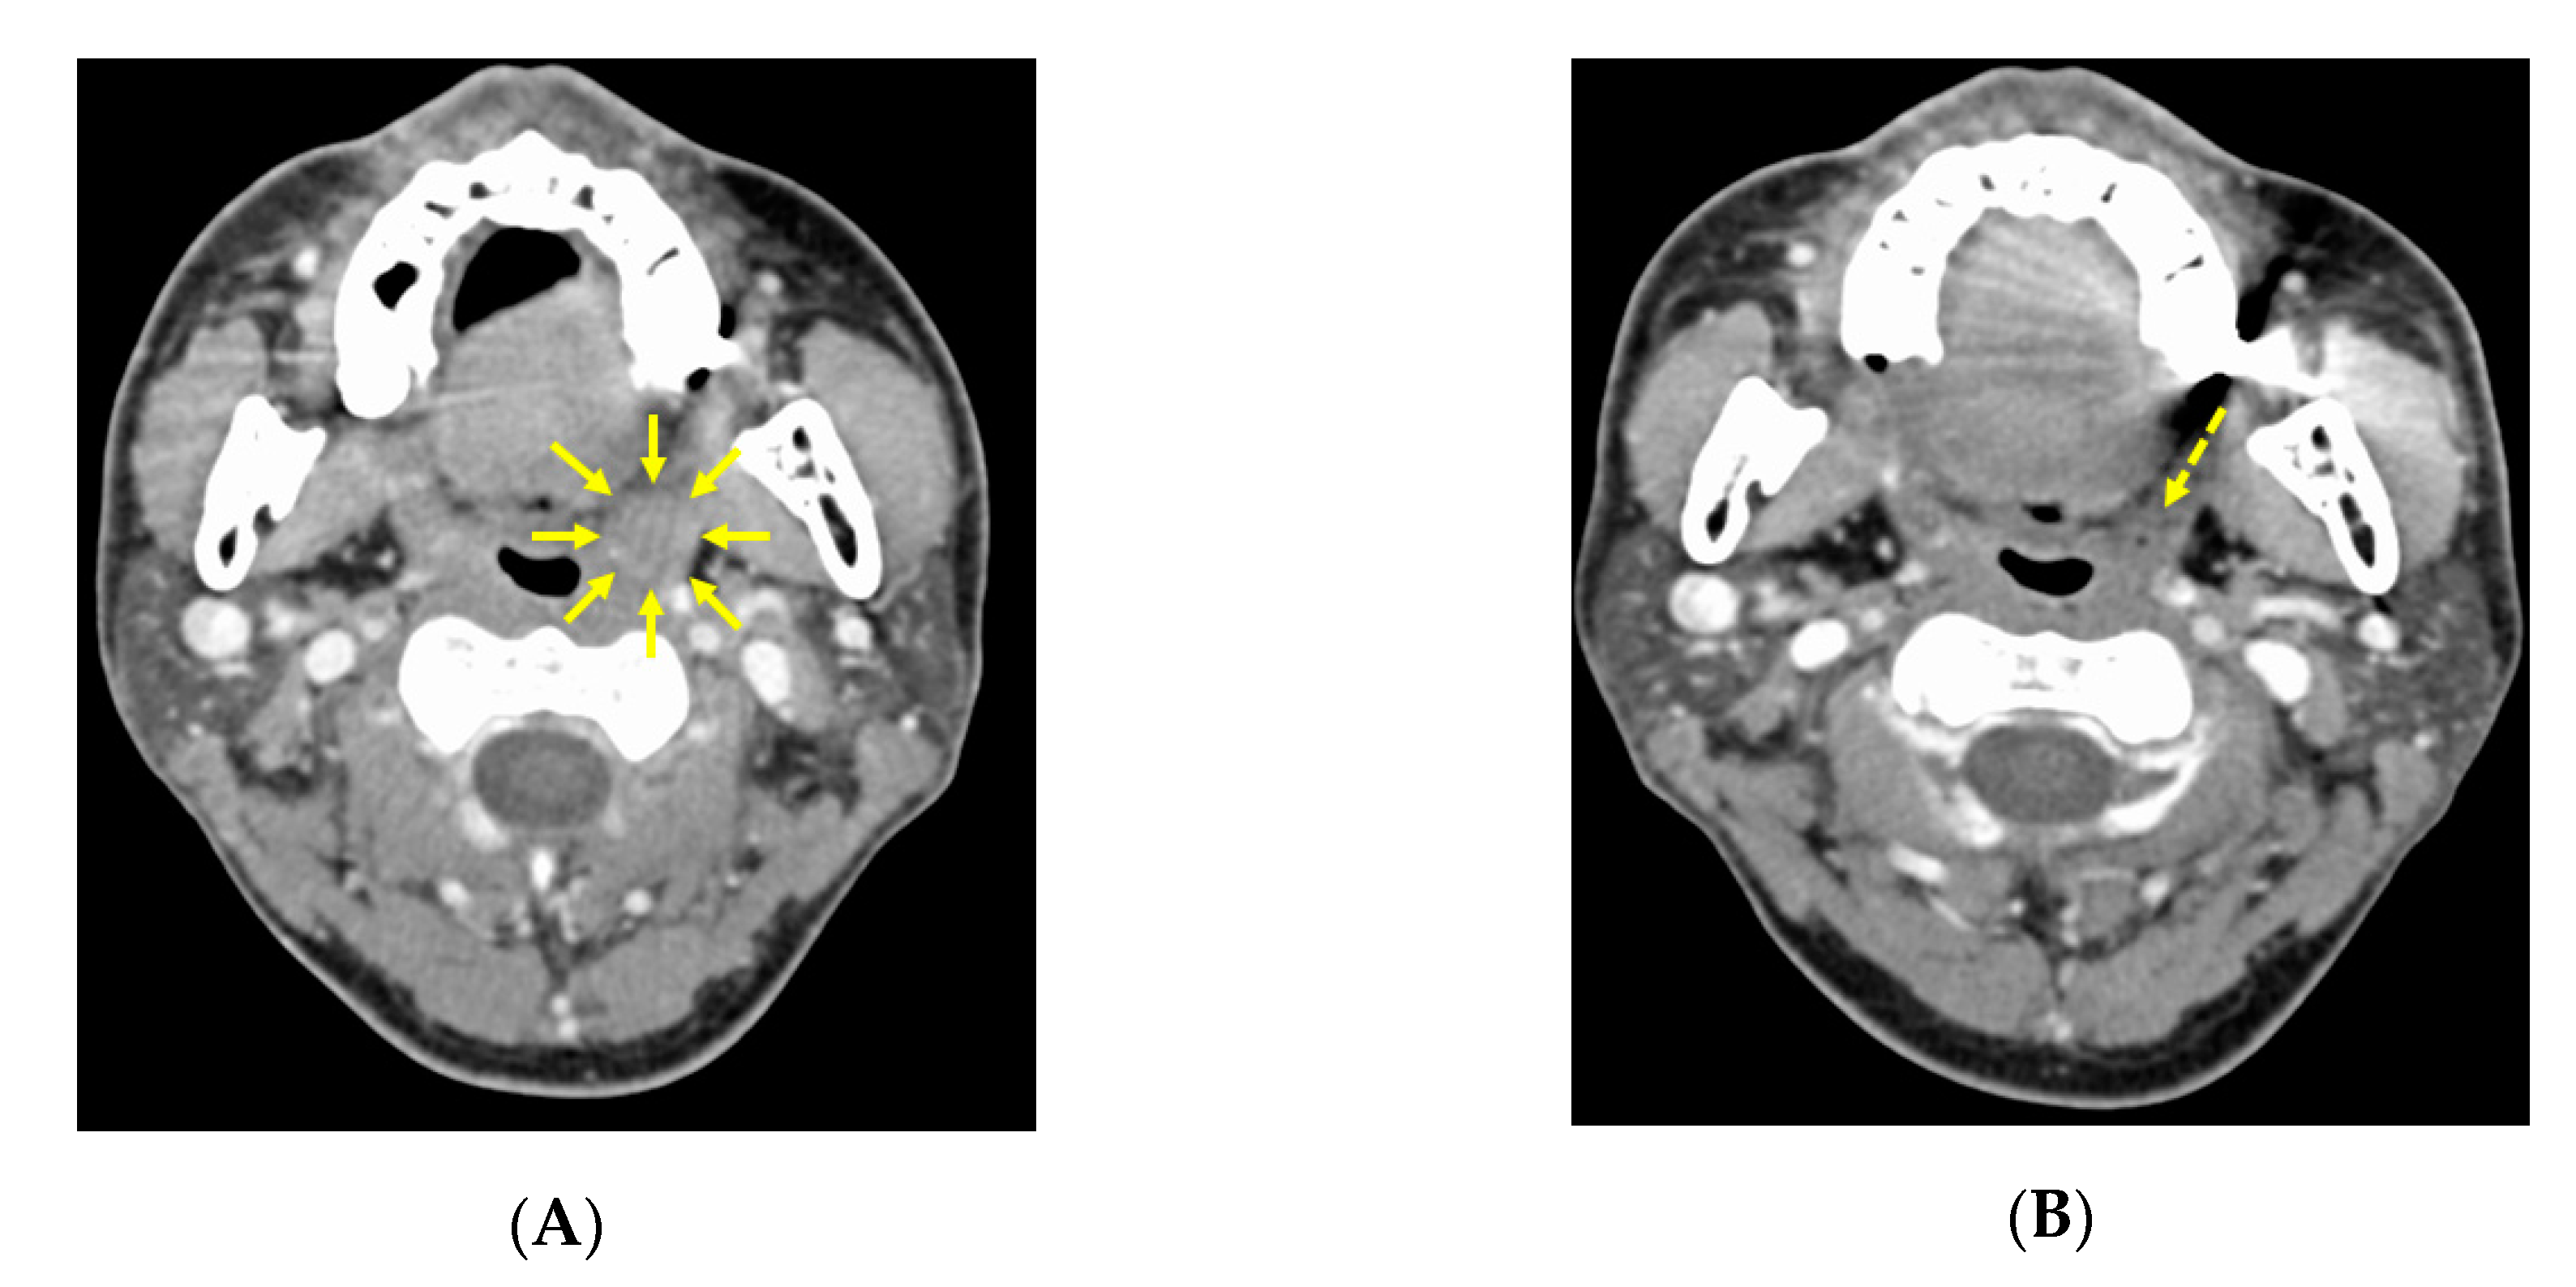

3.2. CT image Findings before and after Neoadjuvant Chemotherapy